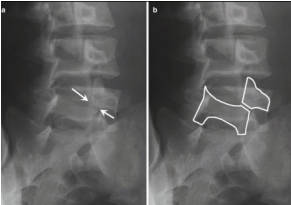

Estenose dos forames intervertebrais

* O forame intervertebral tem que ter formato [—], se perde esse formato = problema

* No caso abaixo há estenose por conta dos [—]

A

redondo

osteófitos